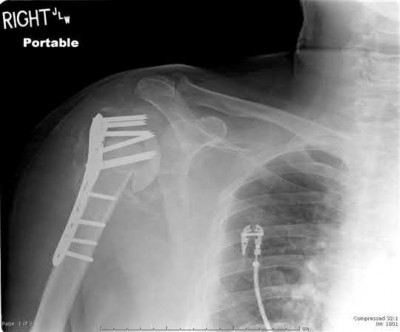

Figures A-C are the radiographs of a 26-year-old male who presents to the emergency department following a motocross accident. Two attempts at a closed reduction by the on-call orthopedic resident were unsuccessful. Figures D and E are the pre-operative axial CT-images that were obtained. The patient undergoes surgical fixation seen in Figure F. Limitations in post-operative dorsiflexion is likely influenced by which of the following?

The rare Bosworth fracture-dislocation is a posterior dislocation of the fibula which becomes entrapped behind the tibia. As demonstrated in this vignette, these injuries are extremely difficult to close reduce secondary to the ridge of the posterolateral distal tibia. The irreducible nature of this injury is a known risk factor for the development of compartment syndrome. The CT images further demonstrate fracture extension to the posteromedial rim (“posterior pilon variant”). In this situation, the only effective method to reduce the fracture is through an open posterolateral approach with the interval between the flexor hallucis longus and the peroneal tendons. This is the same approach that is utilized for fixation of the posterolateral fragment and fibula. Loss of dorsiflexion has been demonstrated following this fracture pattern with posterior fixation. The positioning of the plates in Figure F suggests the

utilization of a posterolateral approach.

Figures A-C: The initial radiographs reveal the posterior subluxation of the talus with associated posterior subluxation of the fibula without significant coronal plane deformity. This deformity should raise the suspicion of a Bosworth fracture-dislocation, especially if closed reduction is not successful. Figures D and E: Axial CT images demonstrating Bosworth fracture-dislocation of the fibula entrapped behind the tibia. Also, note the fracture extension to the posteromedial rim in this posterior pilon variant.

Figure F: Positioning of the plate suggests a posterolateral approach to address both the fibula and posterior malleolus fractures.